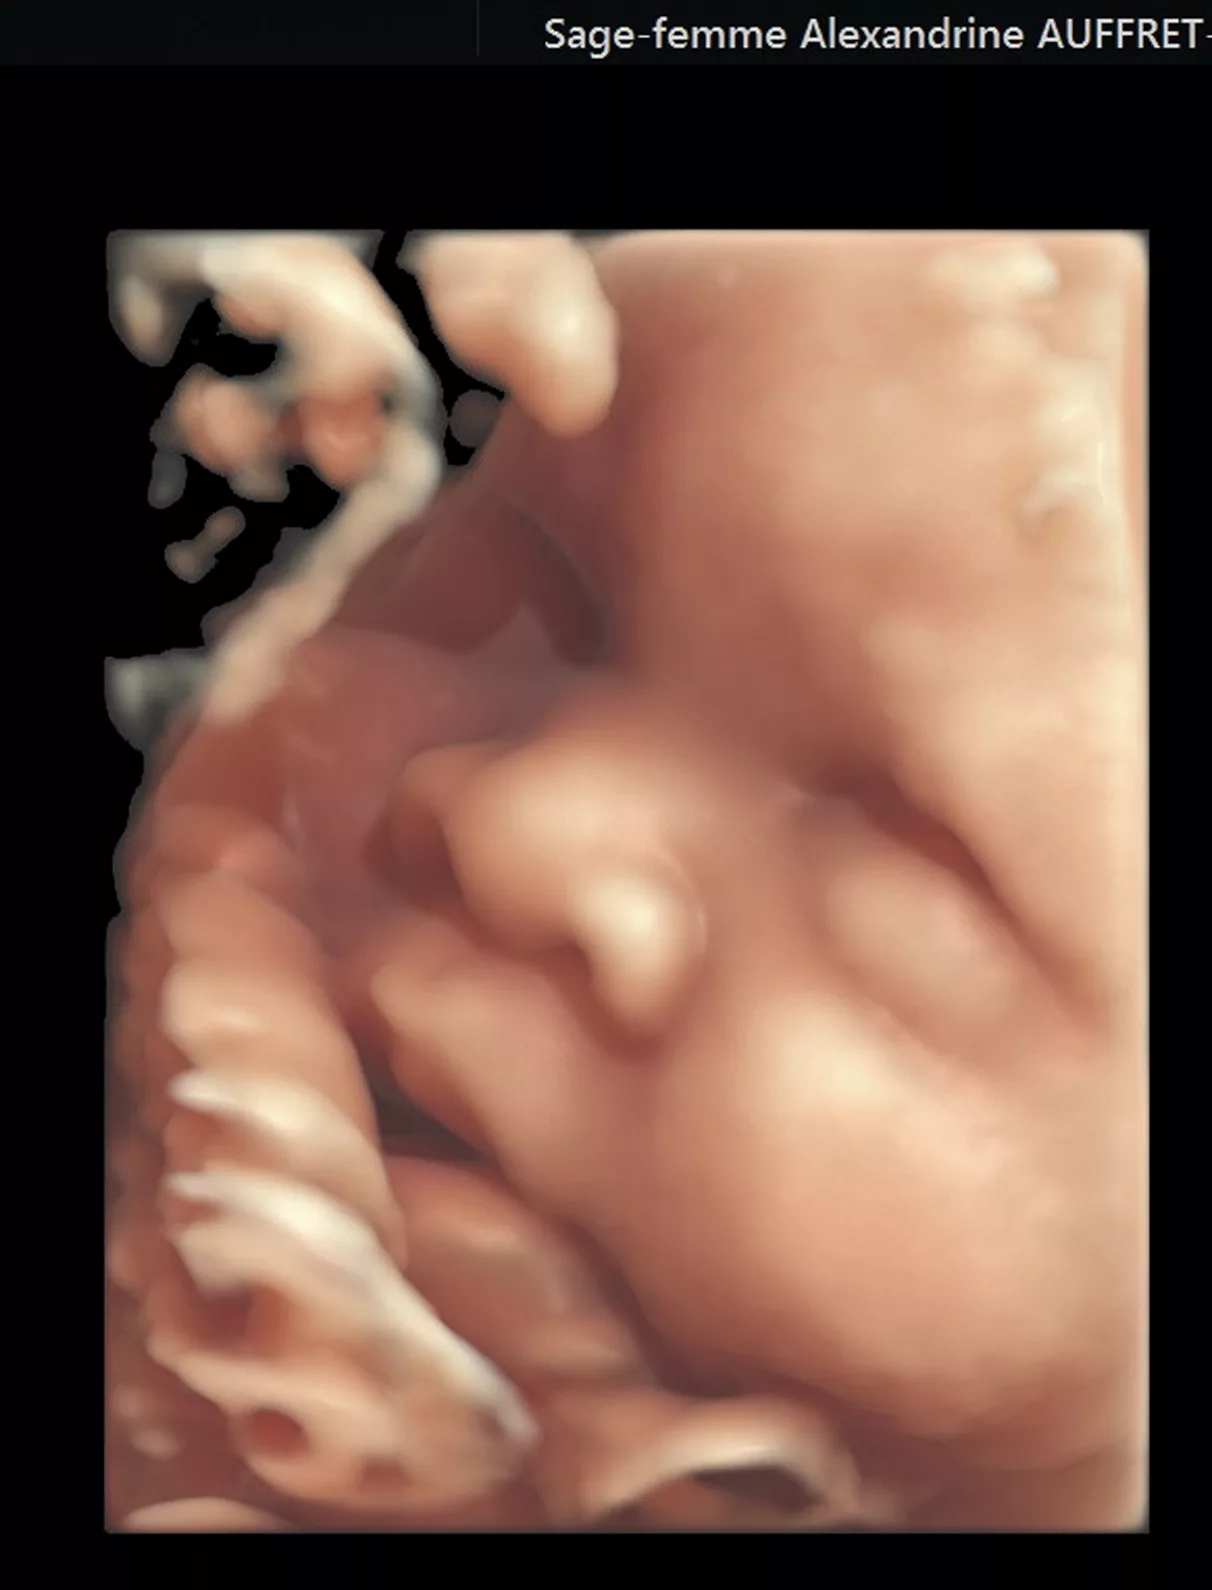

Qu’est-ce qu’une échographie 3D/4D ?

​L’imagerie fœtale en 3D/4D (en 3/4 Dimensions) est obtenue par la reconstruction informatique d’une partie du bébé enregistrée par l’échographe lors de l’examen classique. La sonde d’échographie habituelle balaye automatiquement la partie du bébé qui doit être étudiée. Un logiciel informatique intégré dans l’échographe reconstitue alors une image en 3 dimensions. Il ne s’agit donc pas d’une photographie « réelle » et l’aspect obtenue est souvent imparfait. Il ne doit pas vous « effrayer » car ne correspond en rien à la réalité de votre bébé.

L’échographie en 3D n’est pas toujours réalisable et sa faisabilité dépend de la qualité de la paroi abdominale maternelle, de la position du placenta, de la position, de la mobilité du bébé et de la quantité de liquide amniotique.

L’échographie 3D ou 4D ne présente pas de danger pour votre fœtus.